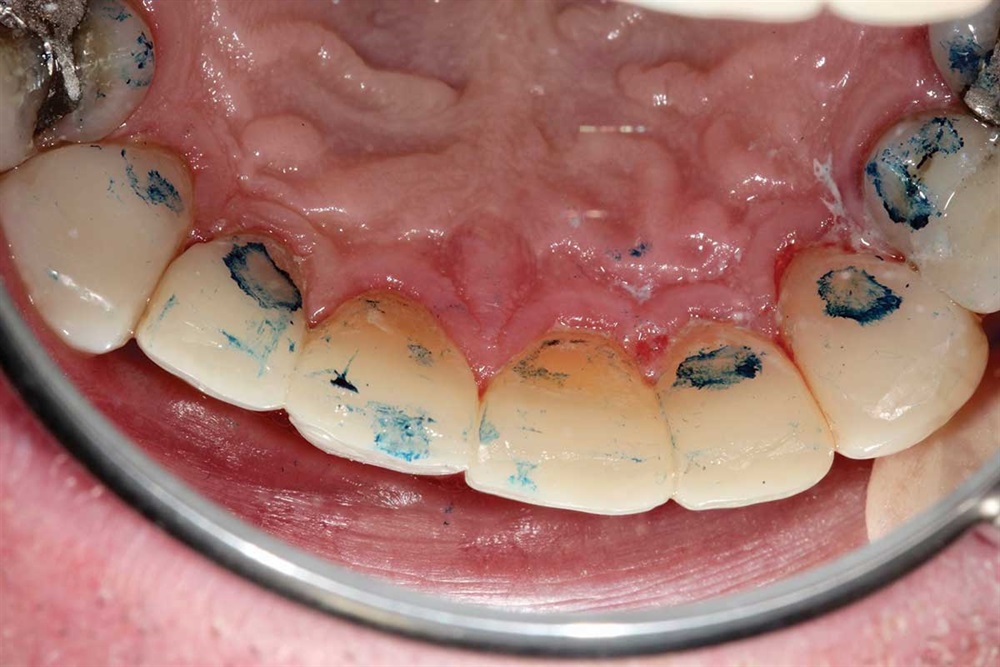

Show Your Work

Fig. 40: Plaque.

Fig. 41: Occlusion being adjusted. I did not increase his vertical when I did the upper teeth.